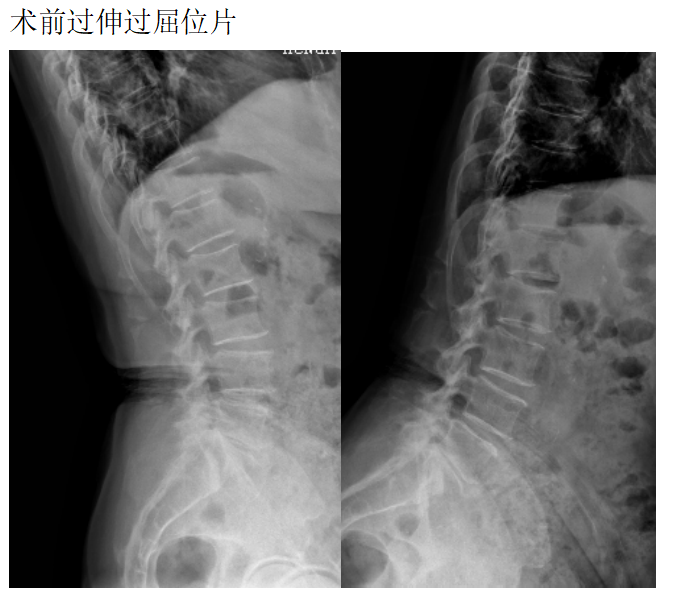

患者女性78岁,主诉:双下肢酸困麻木1年

现病史:1年前出现双下肢酸困麻木,以右侧为主,行走及站立时症状加重,平卧休息稍减轻,未治疗,上述症状持续加重,步行困难,步行能力约100米,为求诊治,现来我院,遂以“腰椎管狭窄症”为诊断收住我科。发病以来,饮食正常,睡眠一般,体力正常,大小便正常。